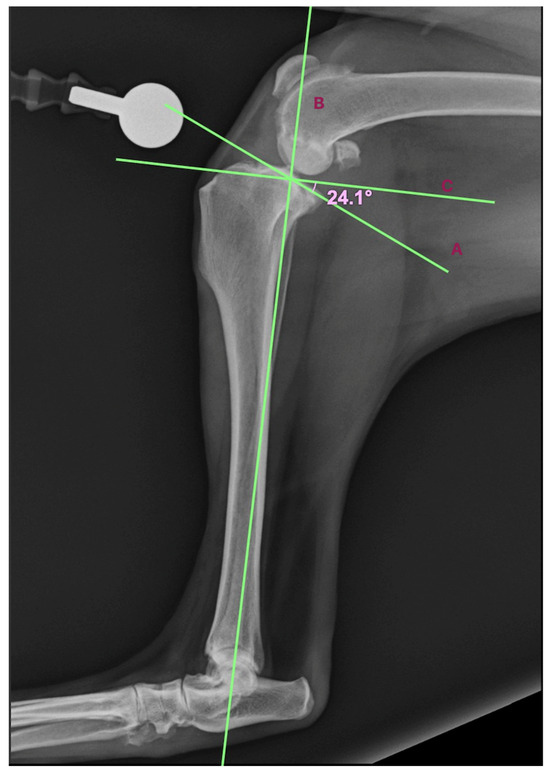

- The line of the tibial plateau slope runs through two landmarks: the cranial attachment of the CrCL (cranial cruciate ligament) and the distal attachment of the CaCL (caudal cruciate ligament).

- The line of the mechanical axis of the tibia runs between the center of the intercondylar eminence of the tibia and the center of the tarsocrural joint.

- The line perpendicular to the mechanical axis of the tibia at the intersection of the other two lines (Figure 1).